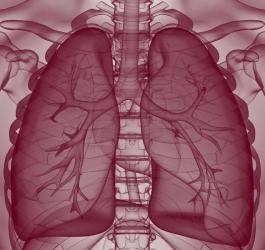

- Pulmonologia